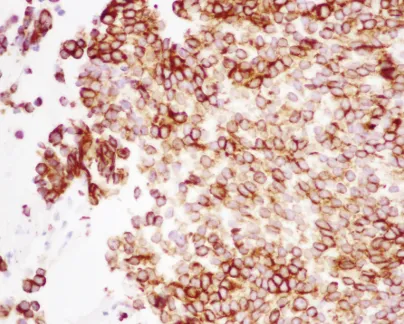

组织学检查显示实性片状低分化细胞,核质比高,可见广泛浸润的小梁和泡状核,伴有中度有丝分裂活性(图5)。

还可见明显凋亡和坏死区域,以及带有纤维黏液样变区域的血管化肿瘤间质。免疫组织化学显示波形蛋白和广谱细胞角蛋白染色阳性(图6)。

图6:显微照片(40倍放大),显示广谱细胞角蛋白弥漫阳性免疫组织化学染色。